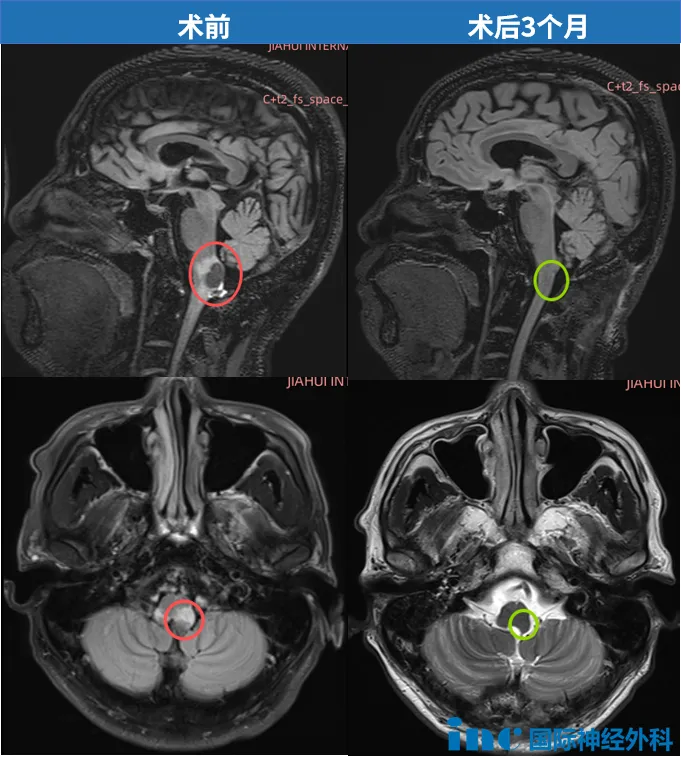

术后3个月,巴教授的随访令W先生彻底安心:影像学显示形态学恢复极为理想。延髓下部血管母细胞瘤已完全切除,未见局部并发症。

同时,脑内水肿已完全消退,脑干下部形态近乎恢复正常。这与患者临床症状的改善高度一致。下一次随访MRI应在大约一年后进行。